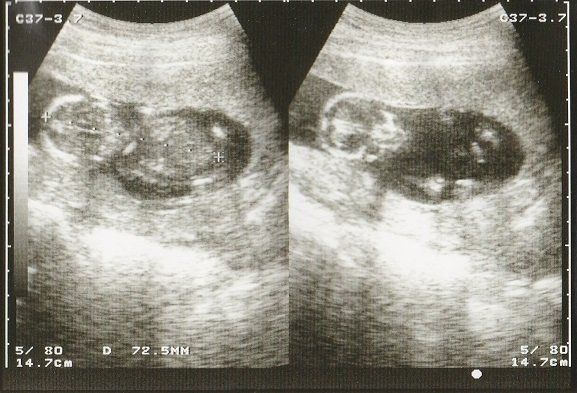

妊娠32週目のエコー写真 おなかもぱんぱんです。

AC(おなかの周囲の長さ)などから、赤ちゃんの推定体重を計算するようです。赤ちゃんのおなかも大きくなっていますが、お母さんのおなかもぱんぱんです。